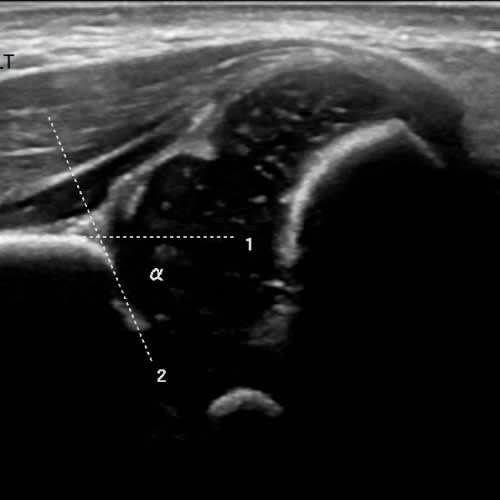

Paediatric Ultrasound is a safe and widely used real time imaging technique which can be performed on infants and children. It uses high frequency sound waves which are produced by a special ultrasound probe, called a transducer. The frequency of these sound waves is higher than can be detected by the human ear. The sound waves bounce off parts of the body and are detected by the probe, then used to create images that can be displayed on a monitor.